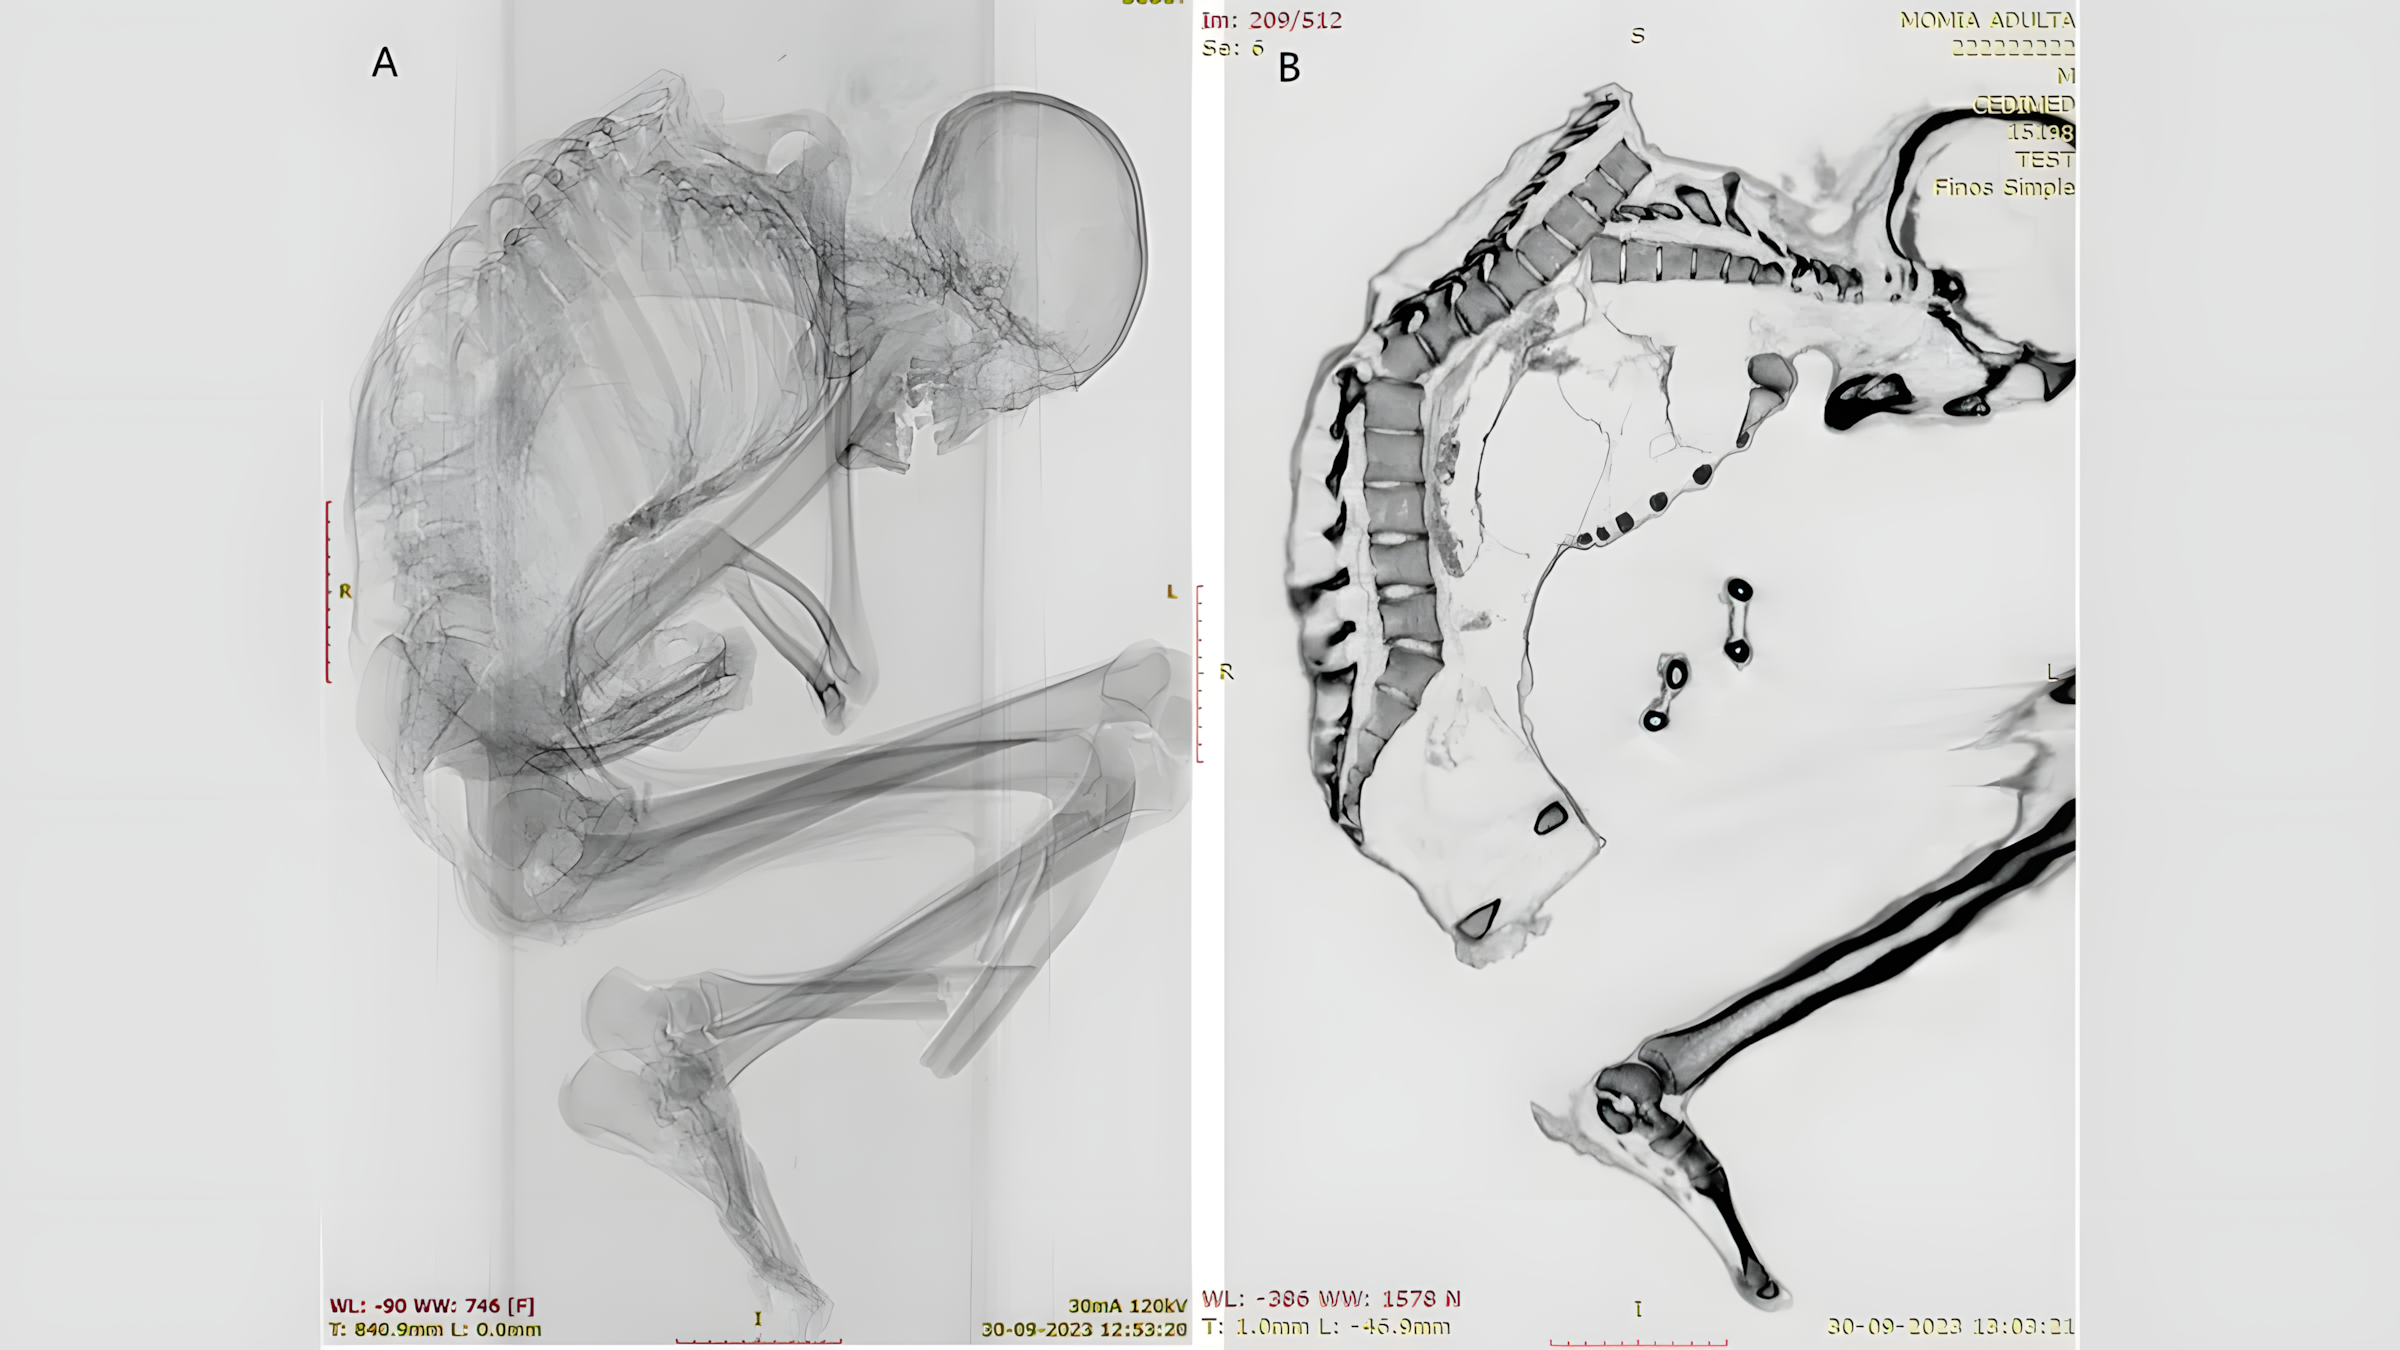

미라화한 광부의 CT 스캔 결과 등, 갈비뼈, 쇄골, 견갑골, 하체 뼈에 심각한 외상성 손상이 발견되었다. (사진 제공: 프란시스코 가리도, 카탈리나 모랄레스)

인간 미라 뼈를 보여주는 엑스레이 두 장. 측면에서 본 미라 뼈는 심하게 어긋난 척추와 하퇴부 골절을 보여준다. 이미지 제공: 프란시스코 가리도, 카탈리나 모랄레스

남성의 척추 윗부분에는 아물지 않은 골절이 여러 군데 발견되었다.

갈비뼈, 견갑골, 쇄골 골절도 있었는데, 이는 상부 등 부위에 "넓은 영역에 걸쳐 둔탁한 충격"이 있었음을 시사하며, "특히 왼쪽 흉곽 윗부분이 가장 큰 충격을 받았음을 보여준다"고 모랄레스와 가리도는 연구 논문에서 밝혔다.

이 충격으로 척추뼈 여러 개가 어긋나고 흉곽이 무너졌다.

또한 연구진은 척추 기저부 근처의 척추뼈에도 골절이 있음을 확인했는데, 이는 초기 상부 등 부상의 결과일 가능성이 높다.

상부 및 하부 척추 손상은 모두 "일반적으로 심각한 척수 손상 및 높은 사망률과 관련이 있다"고 연구진은 덧붙였다.

하지만 남성의 두개골, 목, 팔에는 부상이 발견되지 않았는데, 이는 남성이 머리를 숙인 자세로 충격을 받았음을 시사한다.